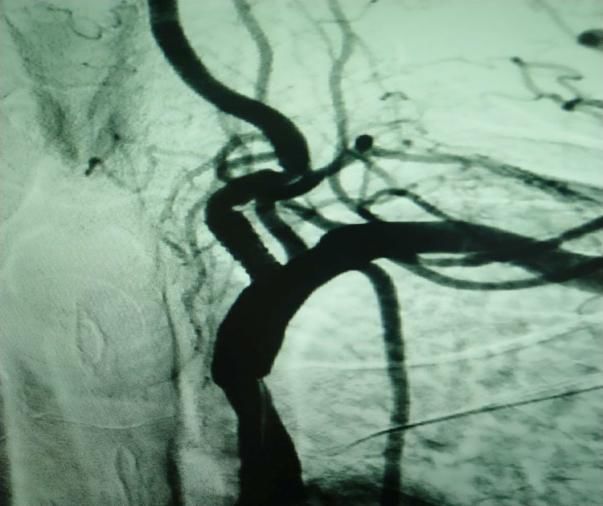

(1)2018年12月12日开展第一例肾动脉支架植入术。

患者:赵某 男性 49岁 岳村镇

图片

术前

术后